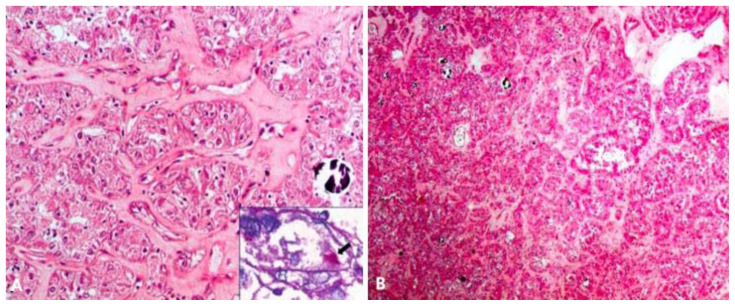

Figure 3.

16 year old female with retroperitoneal alveolar soft part sarcoma.

FINDINGS: Scanner view showing a tumor arranged in an alveolar pattern separated by edematous septae and specks of calcification [H & E, 40x] (A) Higher magnification shows round to polygonal cells, with abundant granular eosinophilic to vacuolated cytoplasm (B)

TECHNIQUE: Microscopic examination using H&E stain, Medium-power view (40x) and High magnification from the core needle biopsy of retroperitoneal mass.

The tumor was a globular, well encapsulated, grey white solid cystic, soft tissue lesion measuring approximately 10×9×6.5 cm in size on gross pathological examination. Cut surface showed a well encapsulated grey white cystic friable tumor, with a wall thickness of 0.2–0.4 cm. The normal left adrenal gland was compressed at one pole by the tumor. Calcified areas were seen within the tumor substance. Microscopic examination revealed a tumor with cells arranged in alveolar pattern separated by thin fibrovascular septae, and focally in solid sheets. Interspersed areas of calcification, hemorrhage and necrosis were identified. Individual tumor cells were round to polygonal with pale granular eosinophilic, friable cytoplasm, coarse chromatin and prominent nucleoli. Presence of intracytoplasmic crystals were noted in few of the tumor cells which were positive for Periodic Acid Schiff (PAS) with diastase. On immunohistochemistry, the tumor cells were focally positive for vimentin and epithelial membrane antigen (EMA), synaptophysin, S100, while negative for cytokeratin, epithelial chromogranin, CD10 and HMB45 (Fig. 3A & 3B). Based on characteristic histopathological and immunohistochemical findings, final diagnosis of alveolar soft part sarcoma (ASPS) of the retroperitoneum was given.